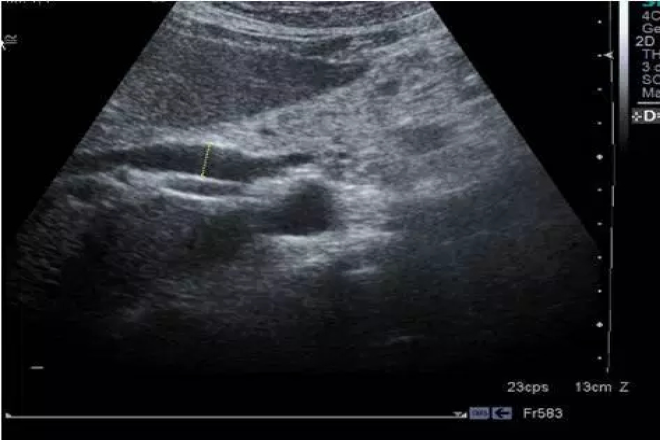

El ultrasonido puede identificar zonas de inflamación pancreática, lesiones hipoecoicas, áreas con ecogenicidad heterogénea y patrones hiperecogénicos. También puede ayudar a identificar la dilatación del conducto de Wirsung y de las vías biliares.